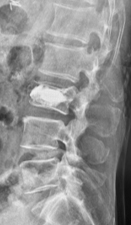

腰の第4番目、5 番目の椎体が感染し、進行性の骨破壊と後弯変形を認めます。経皮的椎弓根スクリューを用いた特殊な方法で、脊椎を安定化しています。

(左)術前の進行性の骨破壊が見られましたが、(右)術後1年では良好な骨癒合が得られています。